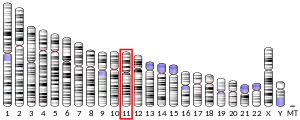

- ↑ Royle NJ, Irwin DM, Koschinsky ML, MacGillivray RT, Hamerton JL (May 1987). "Human genes encoding prothrombin and ceruloplasmin map to 11p11-q12 and 3q21-24, respectively". Somatic Cell and Molecular Genetics. 13 (3): 285–92. doi:10.1007/BF01535211. PMID 3474786. S2CID 45686258.